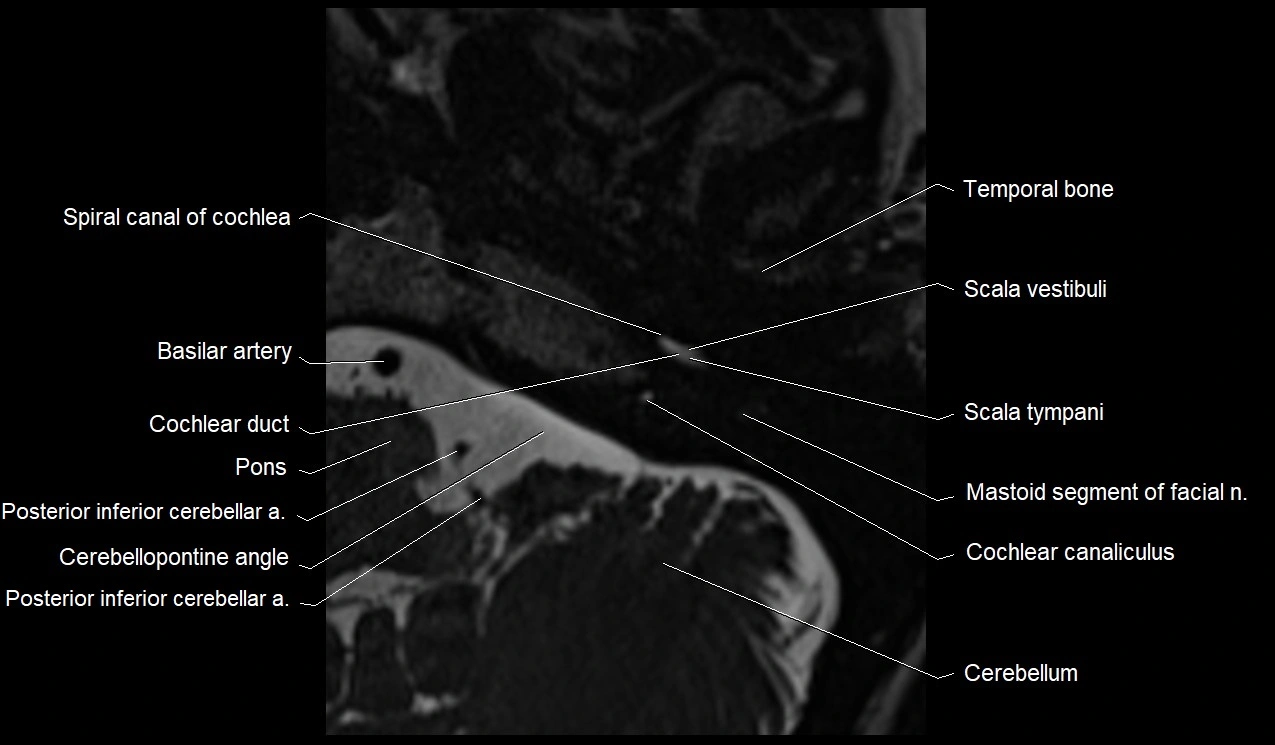

MRI images

image